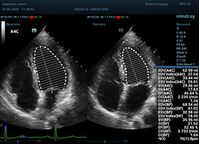

С появлением В режима реализовалась возможность визуализации всех сегментов миокарда из парастернальных и апикальных сечений. Метод Teicholtz в широкой практике сменился методом дисков. Метод дисков, или метод Simpson, позволяет разбить левый желудочек на 20 дисков, с расчетом объема каждого из них. Используя 2 перпендикулярных сечения, апикальные двух и четырех камерное, мы приближаемся к значению реального объема левого желудочка. Исследователь обводит интерфейс эндокард – кровь в фазу диастолы и фазу систолы. Линия простирается от кольца митрального клапана и до кольца митрального клапана, четко разграничивая объем желудочка от предсердия. Для достоверного изменения необходимо использовать ЭКГ канал.

Обводить вручную эти линии занимало много времени, однако результат того стоил. Следующим шагом стало появление Spline технологии, позволяющее расставлять точки и автоматически их соединять. Такой способ планиметрии контура эндокарда значительно сократил время измерения.

Что могут предложить современные приборы? Приборы нашего времени являются мощными вычислительными машинами, способными обрабатывать полученную информацию даже без помощи человека. Система автоматического вычисления фракции выброса – AUTO EF на приборах серии Resona компании Mindray сделает все за вас. За пару секунд прибор сам отыщет нужную фазу сердечного цикла и произведёт измерение и расчеты, а также покажет график изменения объема в сердечном цикле. От Вас требуется только получить качественное 4С и 2С сечение. Впрочем, прибор всегда оставляет возможность коррекции, если доктор имеет свое мнение на расположение точек планиметрии или момента измерения по ЭКГ каналу.